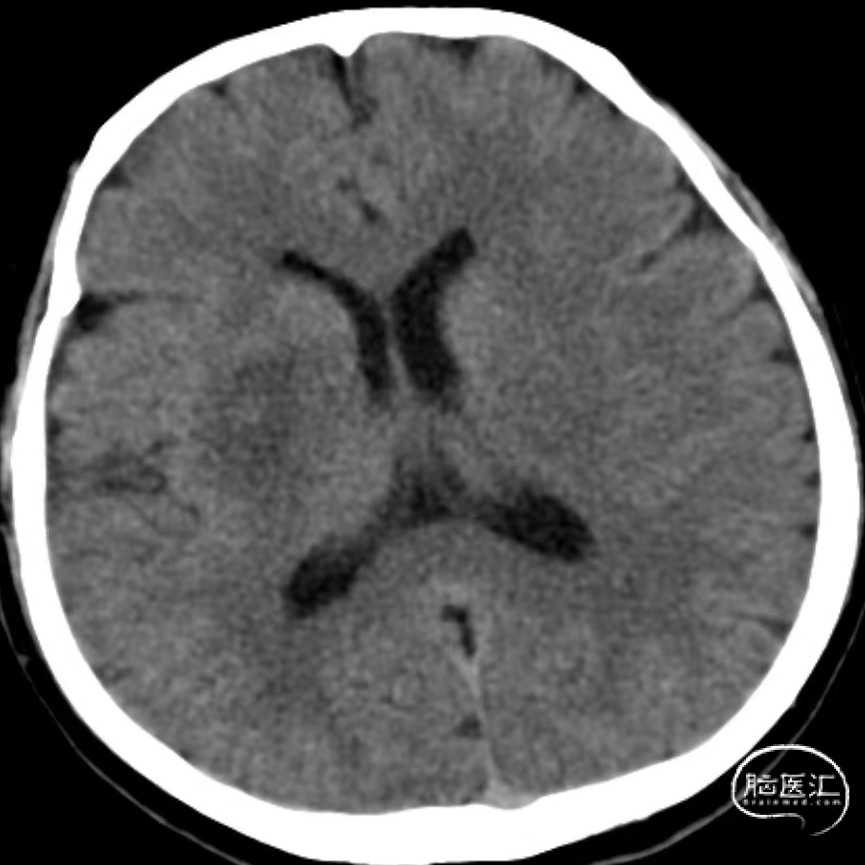

入院时CT:ASPECTS 9分(L1)。